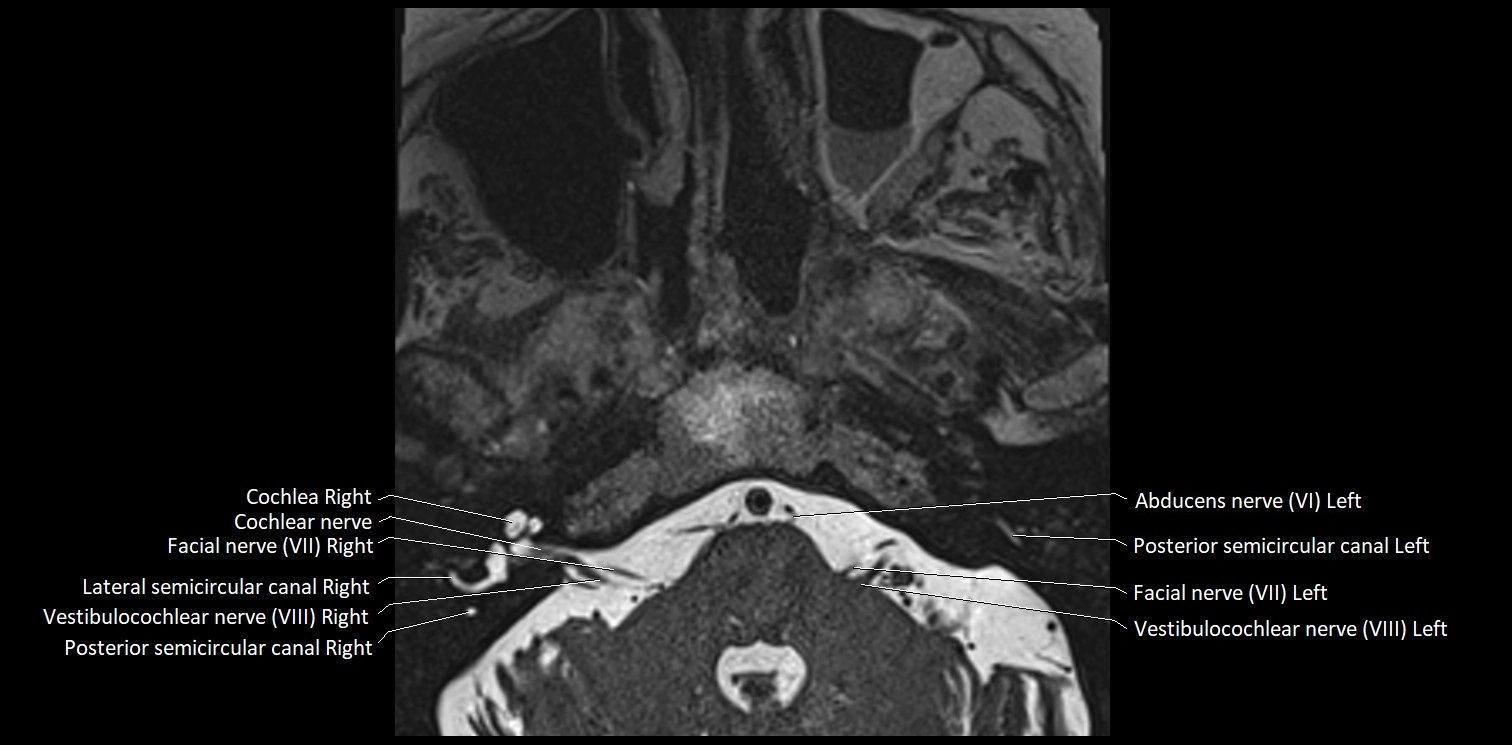

MRI Appearance

• The abducens nerve is a small, thin, linear structure

• Best visualized on high-resolution T2-weighted 3D MRI sequences (e.g., FIESTA or CISS)

• Seen as a hypointense (dark) line running from the brainstem at the pontomedullary junction, traversing the prepontine cistern, and entering Dorello’s canal under the petrosphenoidal ligament, then into the cavernous sinus, and finally the orbit

• May be challenging to visualize in standard MRI due to its small size

• Pathology may be inferred by absence, displacement, or enhancement of the nerve

MRI images

image